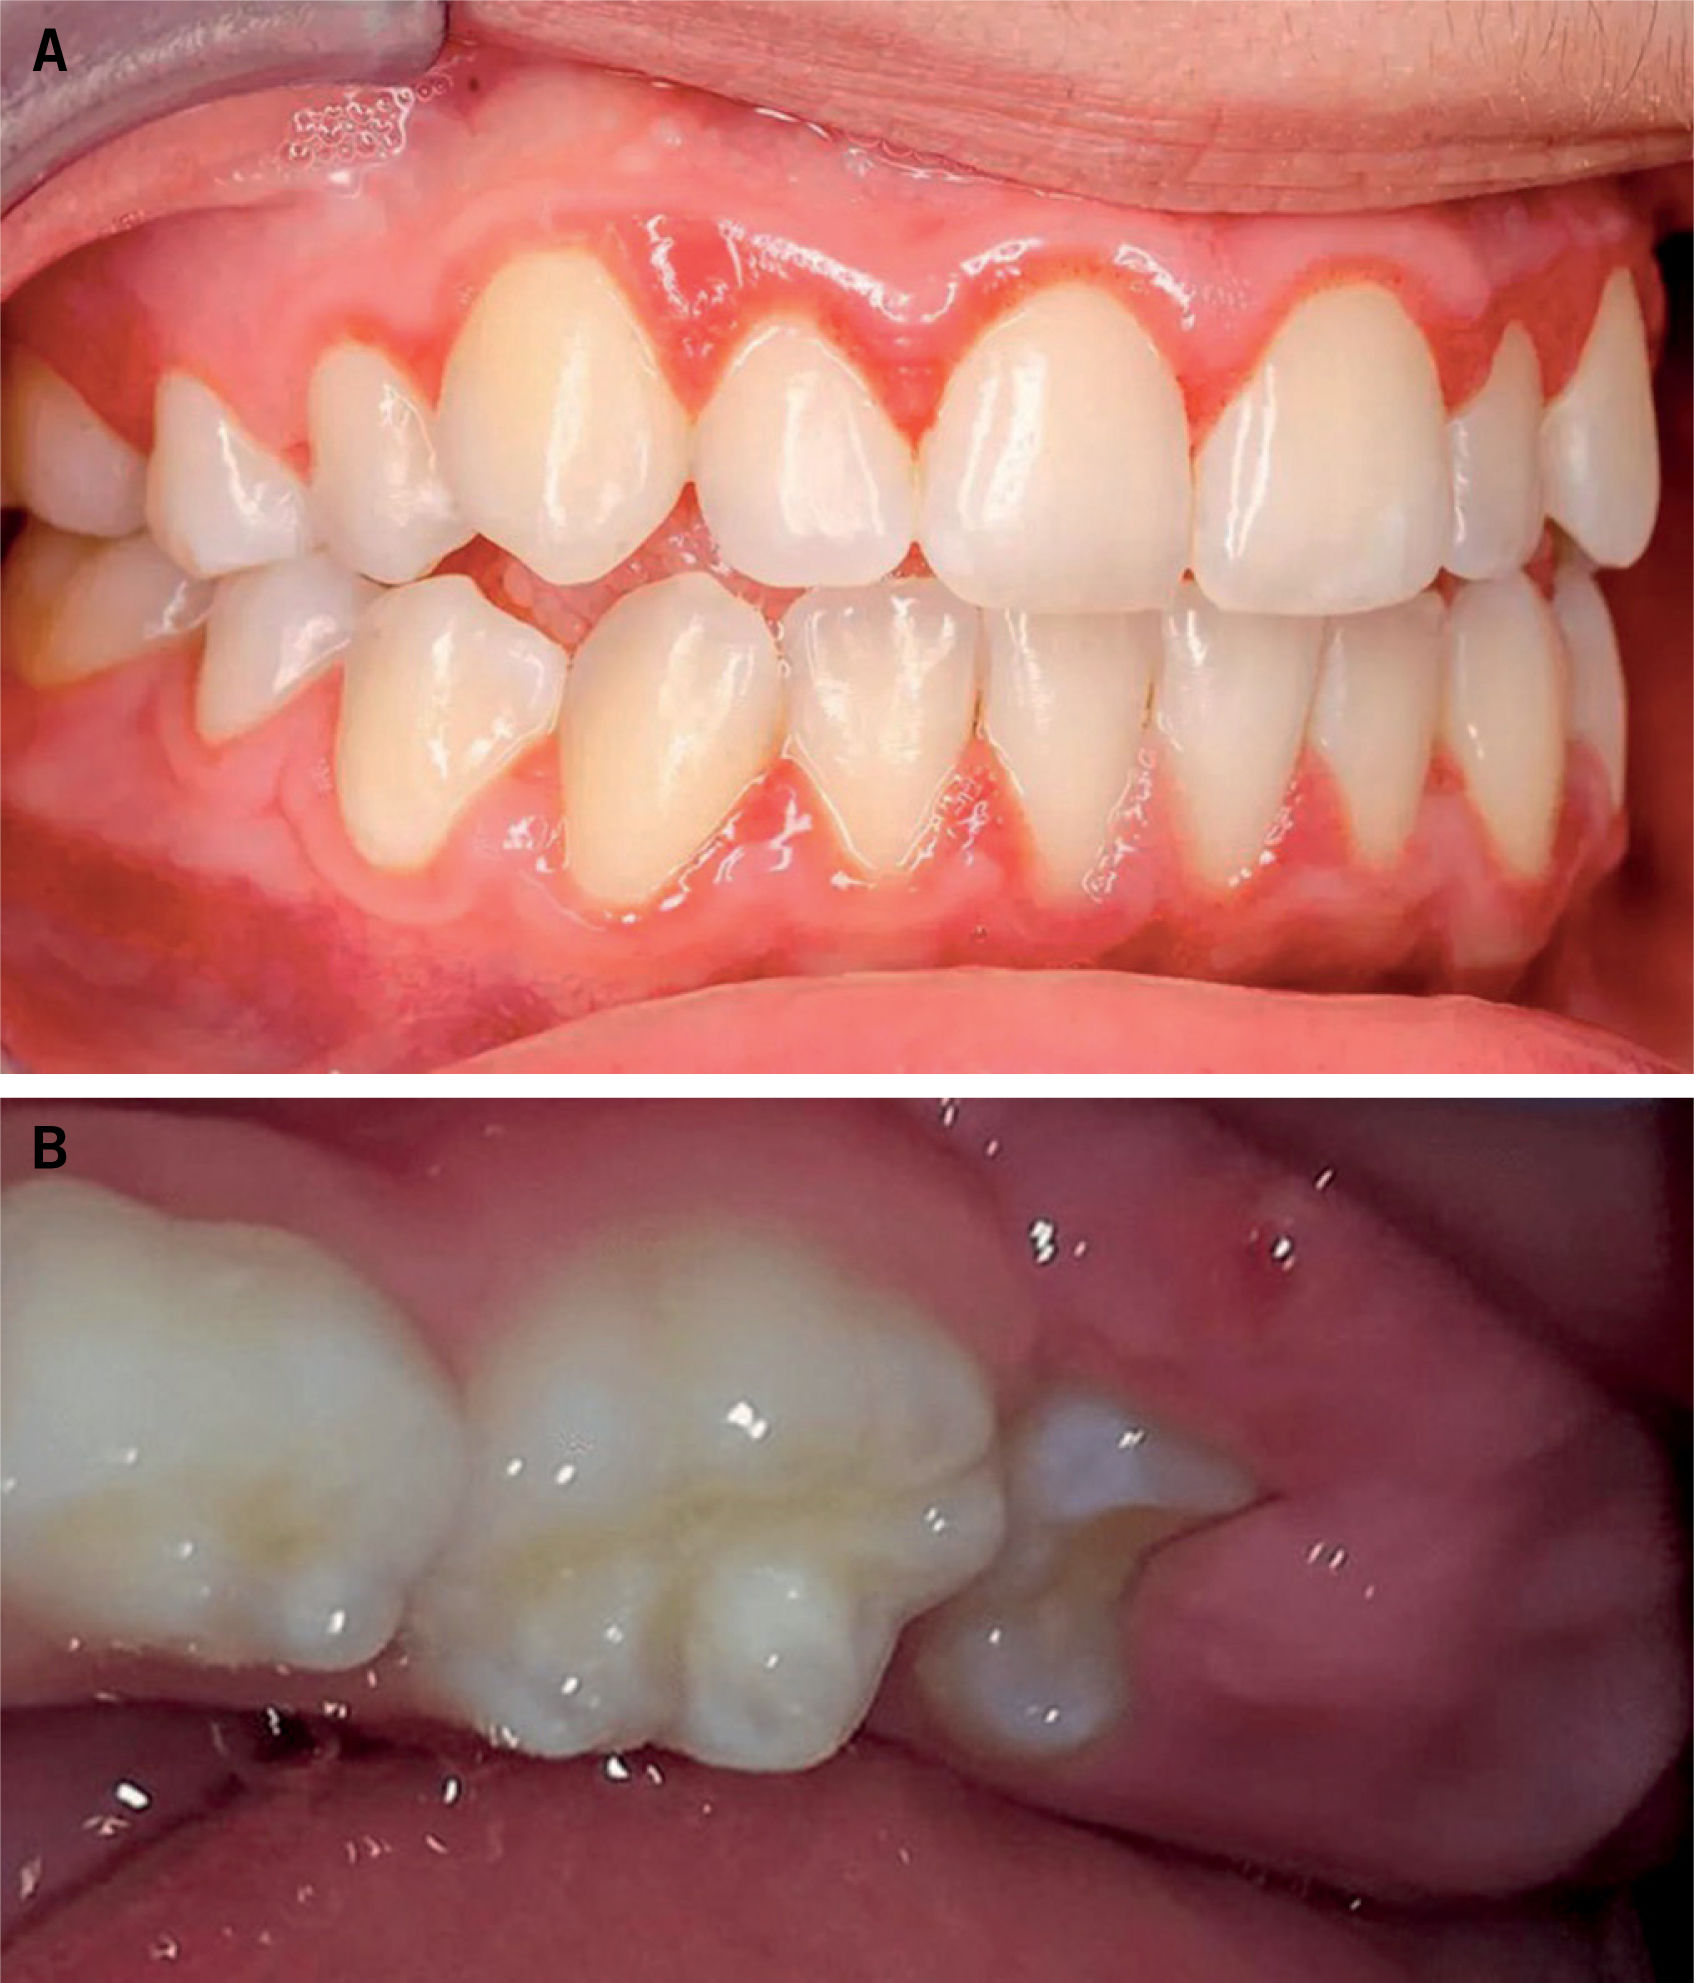

GingivitisPatología causante de inflamación de las encías por acúmulo de placa bacteriana. Es un proceso frecuente en adultos (hasta 50% según las series) pero reversible4.

Clínica. Enrojecimiento y sangrado de las encías, especialmente en el cepillado (fig. 4). Una gingivitis prolongada puede causar hipertrofia gingival (fig. 5).

Pericoronitis: infección en la mucosa que recubre la corona del diente parcialmente erupcionado. Es frecuente en la erupción del tercer molar inferior (muela del juicio), hacia los 20-30 años de edad (fig. 5).